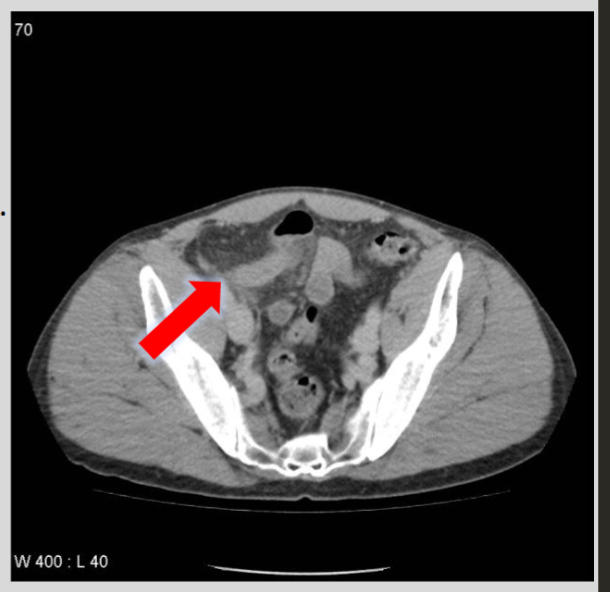

How does computed tomography (CT) create images of the body?

CT uses X-rays and a computer to create cross-sectional images of the body/organs, which are extremely sensitive compared to plain X-ray—>

note** there are 3 planes: axial, coronal, and sagittal imaging

What are the common CT findings for acute diverticulitis?

CT findings usually include focal colonic wall thickening, pericolic fat stranding, and the presence of diverticula.